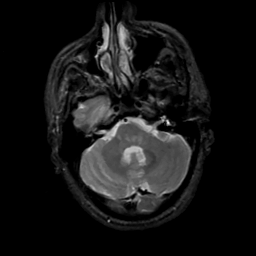

MR Study #5, March 10, 1991 -- Slice #13

[Home][Help][Clinical][Tour 1][Tour 2] Slice 13